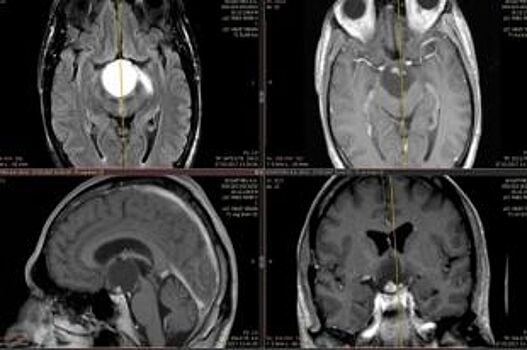

Опухоль атакует голову. Есть ли способы уберечься от рака мозга?

Только за последнее время сразу несколько медийных людей ушли из жизни из-за рака мозга. Наблюдается ли рост этого заболевания? Чего нельзя делать, а что рекомендуется предпринять при генетической предрасположенности к раку, рассказал главный онколог регионального Минздрава Сергей Панченко. Почему болезнь возникает? В мире имеется тенденция к росту числа онкологических заболеваний. На злокачественное новообразование головного мозга приходится приблизительно пять процентов от общего числа раковых заболеваний. Опухоль каждый год диагностируется у четырёх с половиной тысяч пациентов. Из этого числа через пять лет остаётся в живых лишь четырнадцать процентов. Хотя от болезни никто не застрахован, не стоит впадать в уныние. Надо только знать, как выявить болезнь в самом начале развития. Проблема раковых опухолей до конца не изучена. Считается, что в этиологии заболевания играет роль генетическая предрасположенность, неправильное питание, плохая экология, воздействие радиации. Первые признаки Есть ряд симптомов, на которые нужно обратить внимание: Сильные и постоянные головные боли, не проходящие после приёма анальгетиков. Они вызваны давлением опухоли на ткани мозга. Головокружение, потеря равновесия, ощущение, что земля уходит из-под ног. Рвота, которая появляется по утрам или бесконтрольно возникает при резком изменении положения головы. Она может быть не связана с приёмами пищи. Частичное или полное нарушение подвижности некоторых участков тела, нарушение чувствительности конечностей, искажённое восприятие температуры и других внешних факторов. Потеря контроля над функцией мочевого пузыря, затрудненное мочеиспускание. Изменения, связанные с личностью – характер больного меняется, человек может стать вспыльчивым и раздражительным, либо, напротив, чересчур спокойным и равнодушным ко всему, что раньше его волновало. Вялость, апатия, легкомысленность в принятии важных решений, влияющих на жизнь, импульсивные поступки – всё это может быть признаком психических нарушений, возникающих при раке головного мозга. Как правило, злокачественное новообразование головного мозга развивается у людей от 50 до 65 лет. Людям этого возраста надо внимательно относиться к своему здоровью и по необходимости пройти обследование. Особенно это касается тех, у кого есть генетическая предрасположенность к раку. Обследование поможет выявить любое новообразование головного мозга на ранних стадиях и вовремя начать соответствующее лечение. По материалам областного центра медицинской профилактики